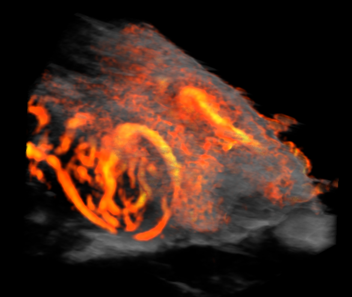

Custom services Cardiology

Myocardial Blood Saturation, Ischemia, Heart occlusion & Strain Analysis

Using the Vevo F2 Lazr-X system, we provide advanced assessment of myocardial oxygenation, ischemia, and cardiac mechanics in rodent models. Through photoacoustic imaging (PA mode) combined with EKV (Electrocardiogram-Gated Kilohertz Visualization), we measure oxygen saturation and hemoglobin concentration within cardiac tissue, enabling precise detection of ischemic regions. Additionally, we offer Vevo Strain analysis, a high-resolution speckle-tracking technique for quantifying myocardial deformation and contractility, providing deeper insights into cardiac function under physiological or stress conditions.

This integrated approach supports studies on cardiovascular disease progression and therapeutic interventions.